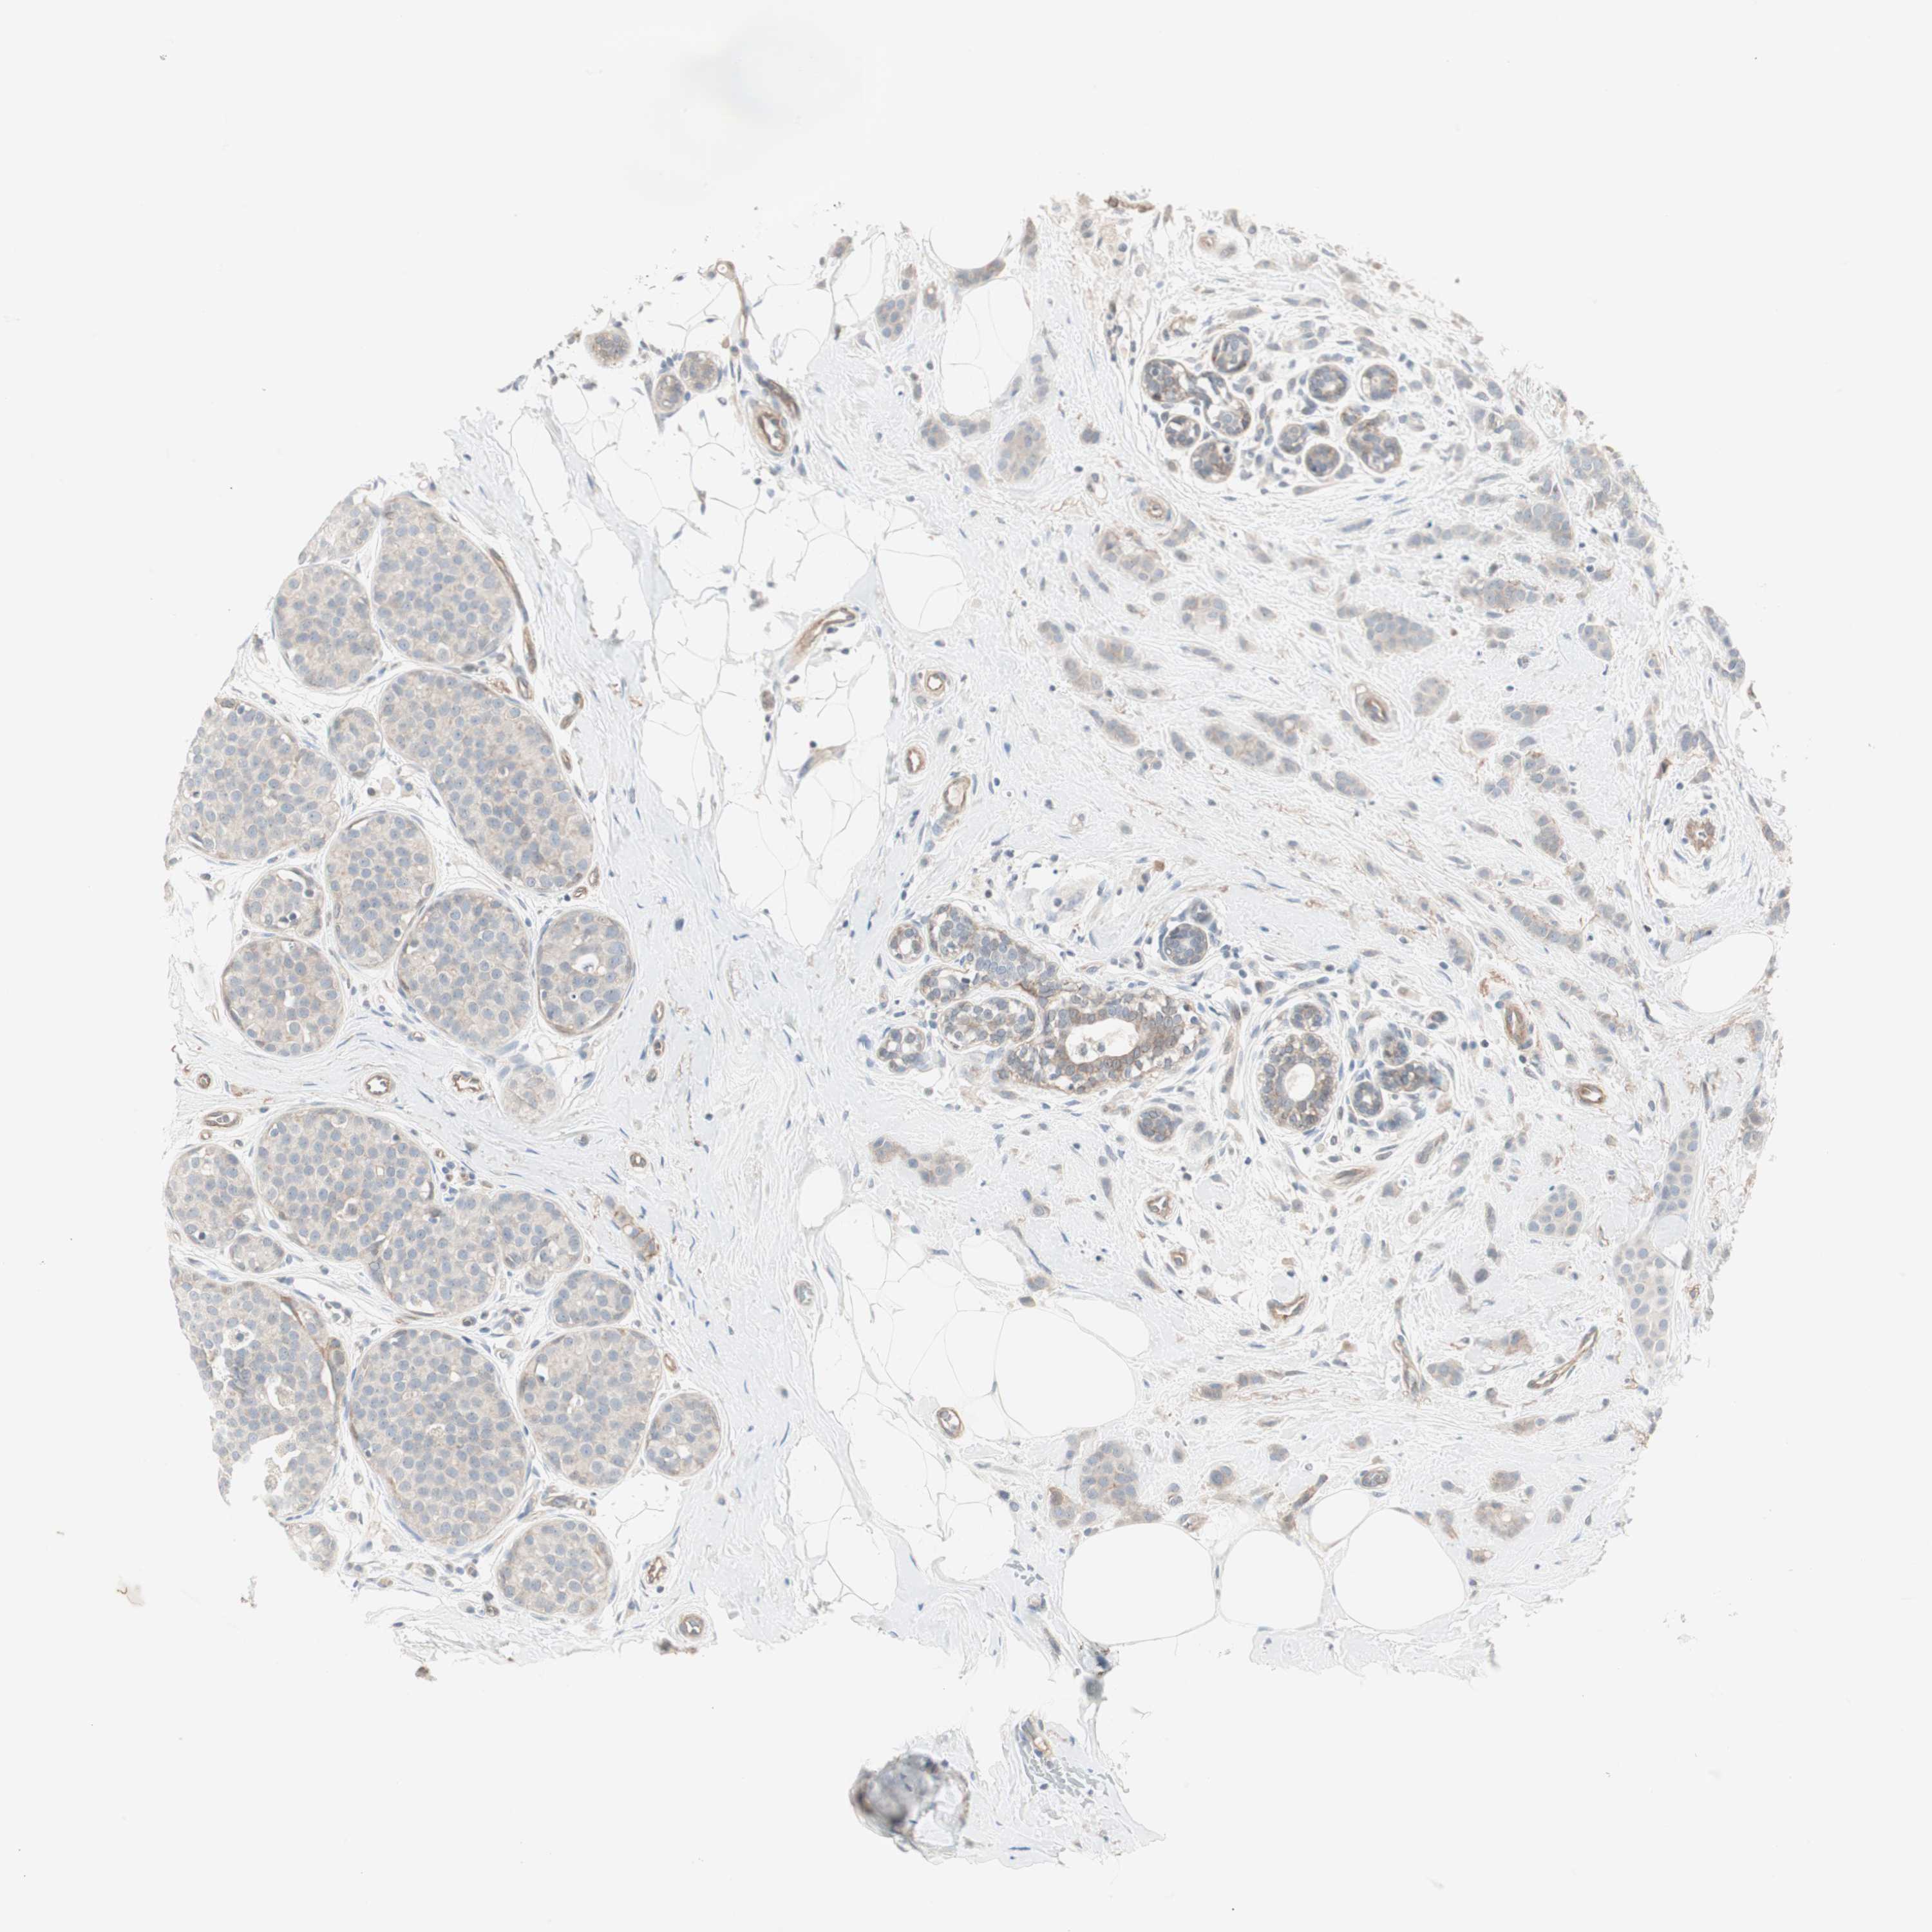

BRCA TCGA BRCA VALIDATION PROTEIN EXPRESSION